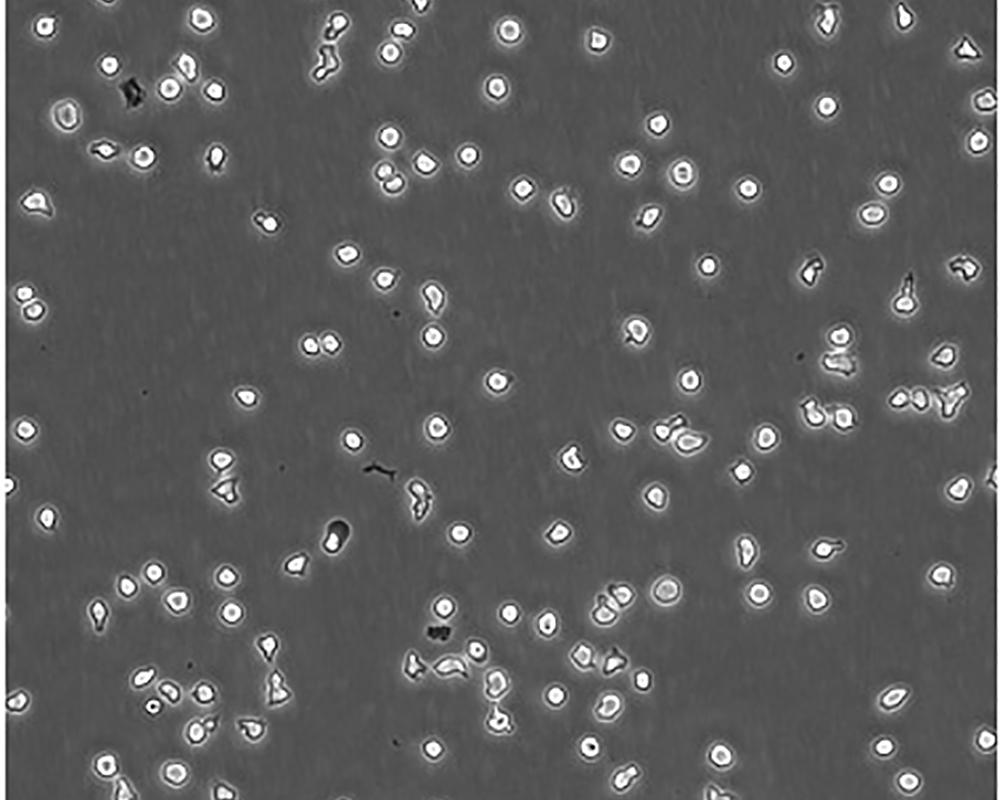

生長(zhǎng)特性 suspension

形態(tài)特征 lymphoblast

傳代方法 Maintain cell density between 2×10^4 and 4×10^4 viable cells/mL.

細(xì)胞描述 一位套細(xì)胞淋巴瘤患者的巨細(xì)胞變種顯示白血病轉(zhuǎn)變,從其外周血單核細(xì)胞出發(fā)建立了MCL細(xì)胞株JeKo-1。 JeKo-1細(xì)胞EB病毒陰性,并表達(dá)一種B細(xì)胞表型的IgM。 細(xì)胞過表達(dá)cyclin D1, Bcl-2, c-Myc 及 Rb 蛋白。 Bcl-1/J(H)基因重排得到了PCR證實(shí)。 JeKo-1細(xì)胞在SCID小鼠中高成瘤。 [PubMed: 9753063]